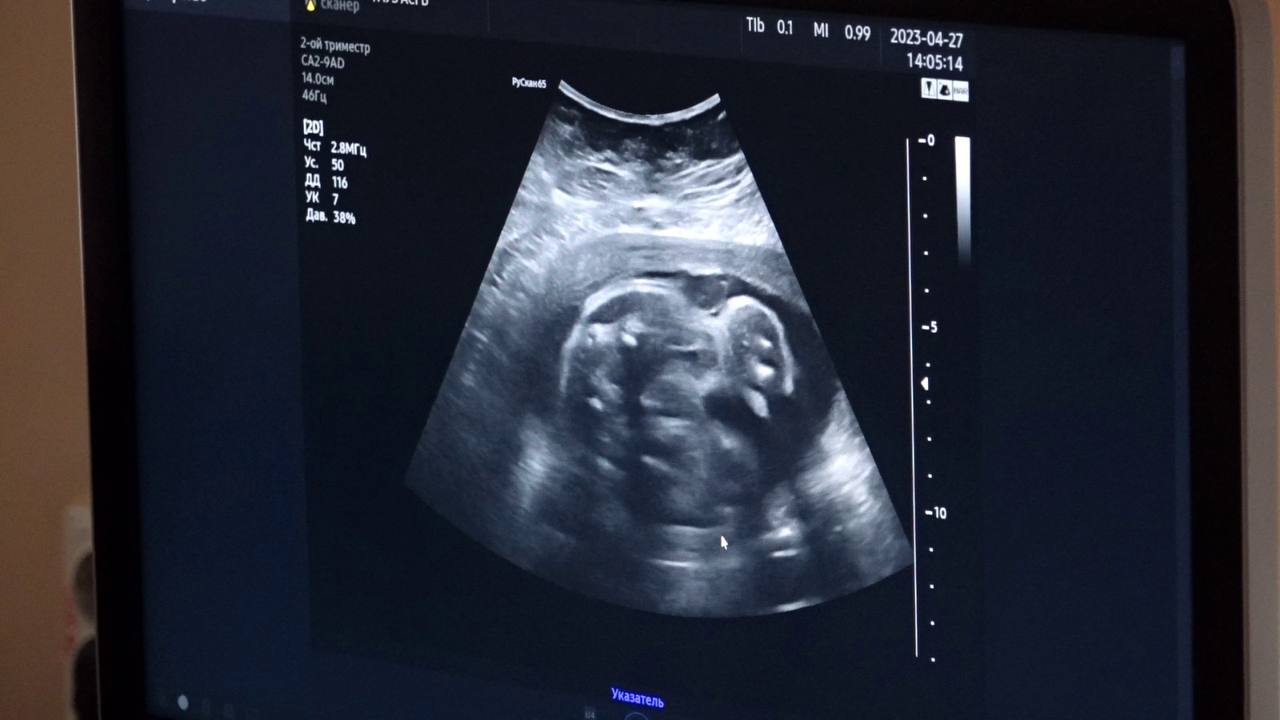

В Мариинскую городскую больницу им. В.М. Богониса закуплена стабилоплатформа с биологической обратной связью и передвижной ультразвуковой аппарат. Также в Анжеро-Судженскую городскую больницу им. А. А. Гороховского поступил передвижной ультразвуковой аппарат для исследования сердца и сосудов «РуСкан 65».